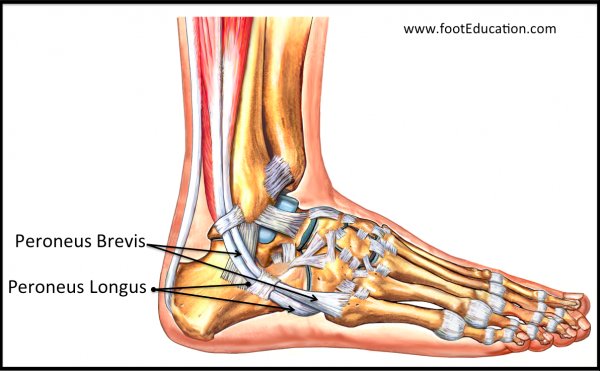

대부분 보존적인 치료를 하며, 통증이 심하거나 생활에 지장이 있는 경우 부골 제거술을 시행해 볼 수 있습니다. (부착된 인대 들도 함께 제거될 수 있으므로, 수술시 인대 부분의 생역학을 잘 고려해야합니다.)